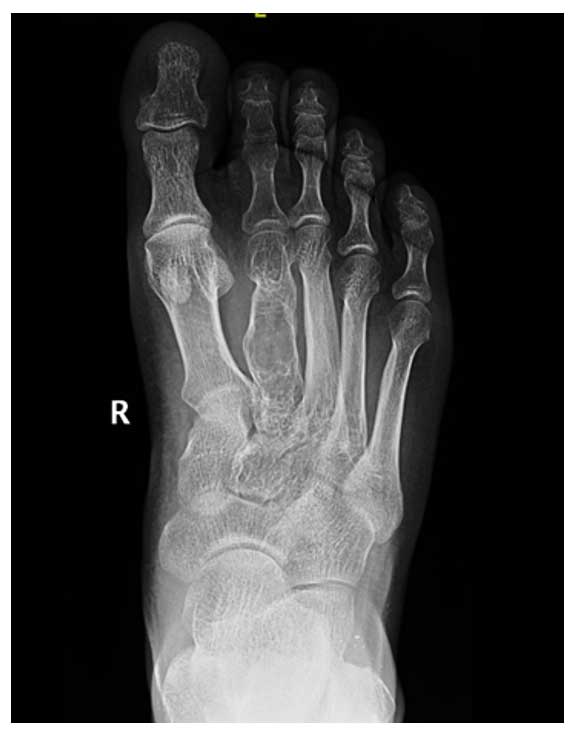

Ameliyat Öncesi: Röntgende ayak 2. metatars kemiğinde litik lezyon ve düzensizlik görülmekte.